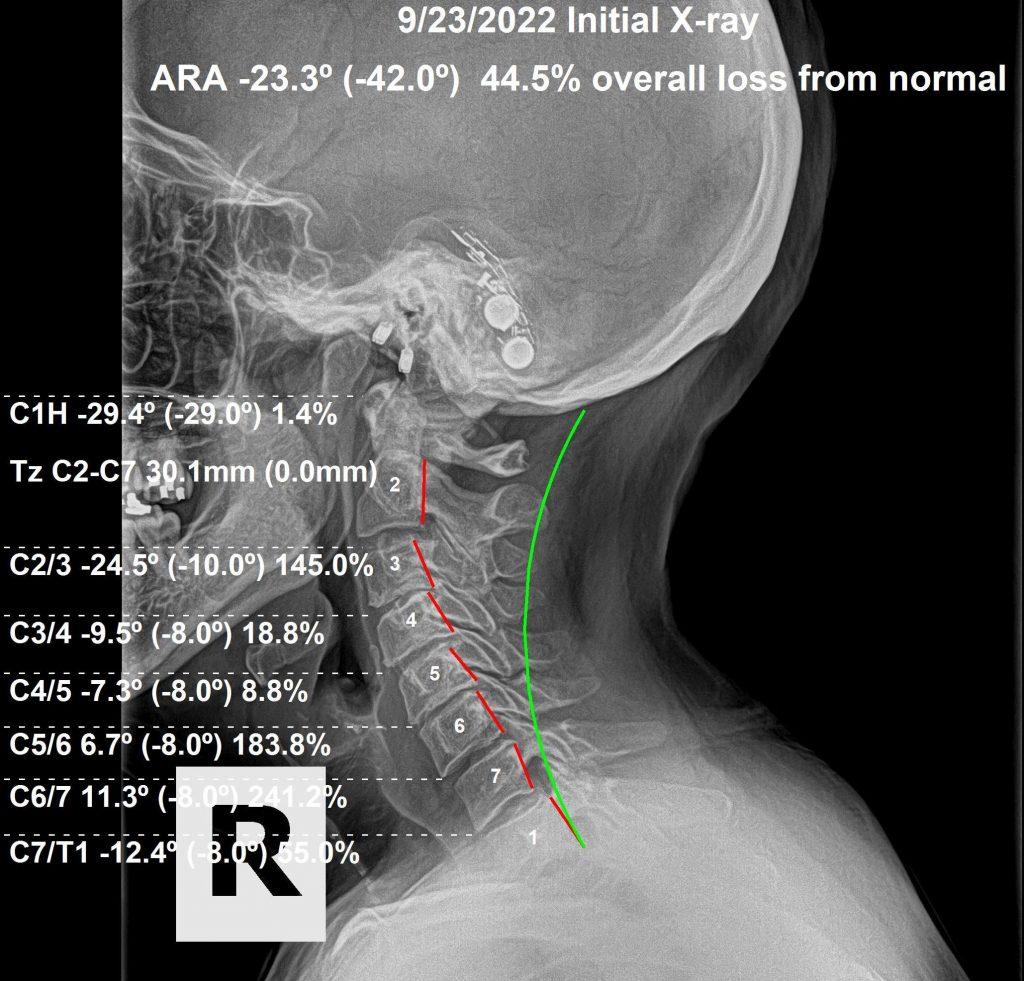

Before chiropractic care after auto accident — spinal alignment

Before

In this case, we saw a 64-year-old female who was involved in a rear-impact MVA. The challenge when treating someone older after an MVA is that underlying spinal degeneration already exists. That subluxation degeneration creates weakness — and when you traumatize existing weakness, that area is injured far worse than the stronger, healthier areas of the spine.

By God's grace, she had been receiving sporadic chiropractic care before the accident, so she was in decent shape before suffering the injuries. Looking at her before and after X-rays, the improvement in alignment is significant. She gained 13 degrees of better curvature. Her forward head posture was reduced, taking significant pressure off her neck muscles. Because we corrected just these 2 factors, she gained better neck movement than she had before the accident. Yes — the neck pain, paresthesias, and headaches resolved. At her age, with advanced degeneration already present, the improvement in spinal alignment is a testament to the innate healing ability of the body.